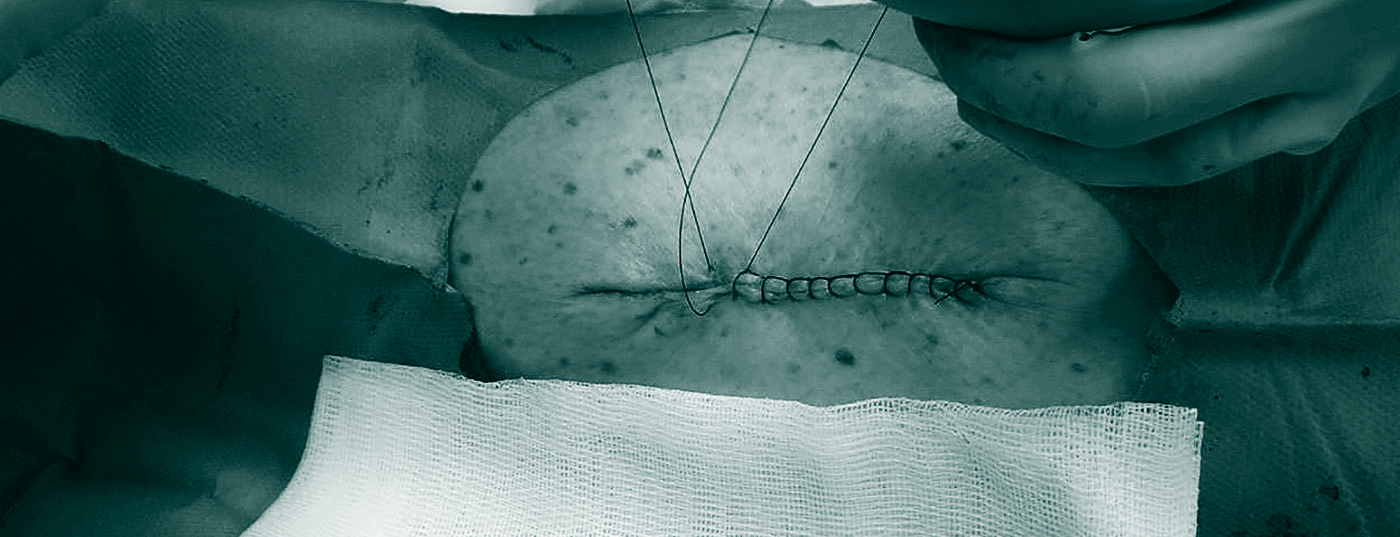

Dermatochirurgie von Hauttumoren für die Praxis

In Anbetracht der massiven Zunahme von Hautkrebs gewinnt auch die Dermatochirurgie an Bedeutung. Viele Hautkrebspatienten können mit Biopsien und Exzisionen in der Praxis diagnostiziert und behandelt werden. Neben dem Beherrschen der einfachen chirurgischen Techniken ist auch die Erfahrung mit anderen, nicht-chirurgischen Verfahren relevant. Ebenfalls wichtig sind Kenntnisse, wann eine Überweisung für aufwändigere Interventionen, wie zum Beispiel Mohs-Chirurgie, notwendig ist.